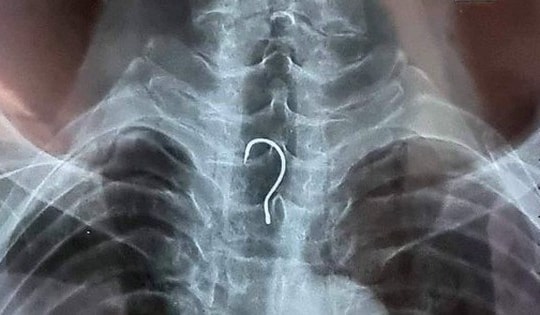

Gắp lưỡi câu mắc trong thực quản cụ già 83 tuổi

Các bác sĩ tại Bệnh viện Đa khoa tỉnh Hà Tĩnh vừa nội soi gắp thành công một lưỡi câu dài gần 4cm mắc trong thực quản của bệnh nhân.